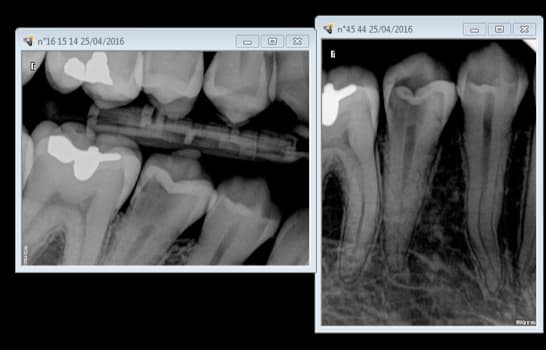

Rentrons dans le vif du sujet Ces 2 cas justifient ils de recourir à un inlay core ?

Et tant qu'on y est quelle cotation pour ces radios. ( patiente consulte pour des douleurs secteur 1)